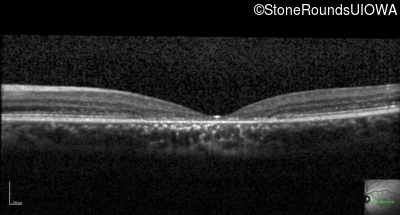

Optical Coherence Tomography - Right - 20/125

Exemplar / OCT Stack

Optical Coherence Tomography - Left - 20/125